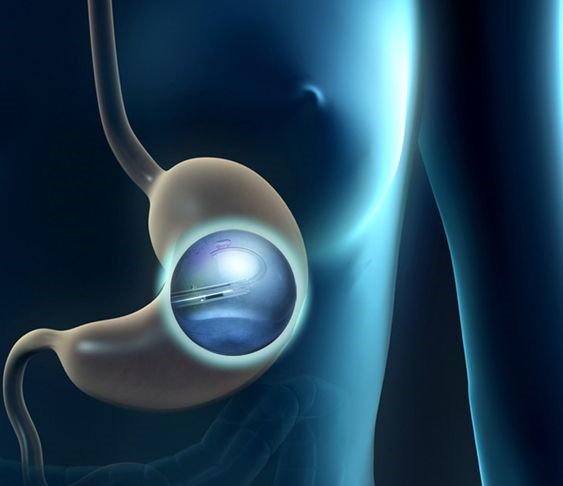

تعتبر عملية بالون المعدة واحدة من الخيارات الشائعة لفقدان الوزن، وتساعد الكثير من الأشخاص في الوصول إلى أهدافهم الصحية. ومع تزايد العيادات التي تقدم هذا النوع من الخدمات في الرياض، يصبح من المهم اختيار العيادة المناسبة. في هذه المقالة، سنقدم لك دليلً...

تعد عملية بالون المعدة واحدة من الخيارات الشائعة لفقدان الوزن للأشخاص الذين يعانون من السمنة أو زيادة الوزن. إنها تتضمن وضع بالون مملوء بالغاز أو السائل داخل المعدة، مما يساعد على الشعور بالشبع وتقليل كمية الطعام المتناولة. في هذه المقالة، سنستعرض ال...

تعد مشكلة الوزن الزائد من أكثر التحديات الصحية انتشارًا في الوقت الحالي، ويبحث الكثيرون عن حلول فعالة وآمنة لإنقاص الوزن. يعتبر بالون المعدة في الرياض أحد الخيارات البارزة التي توفر حلاً غير جراحي لفقدان الوزن. لكن هل هذا الإجراء مناسب للجميع؟ في هذا...